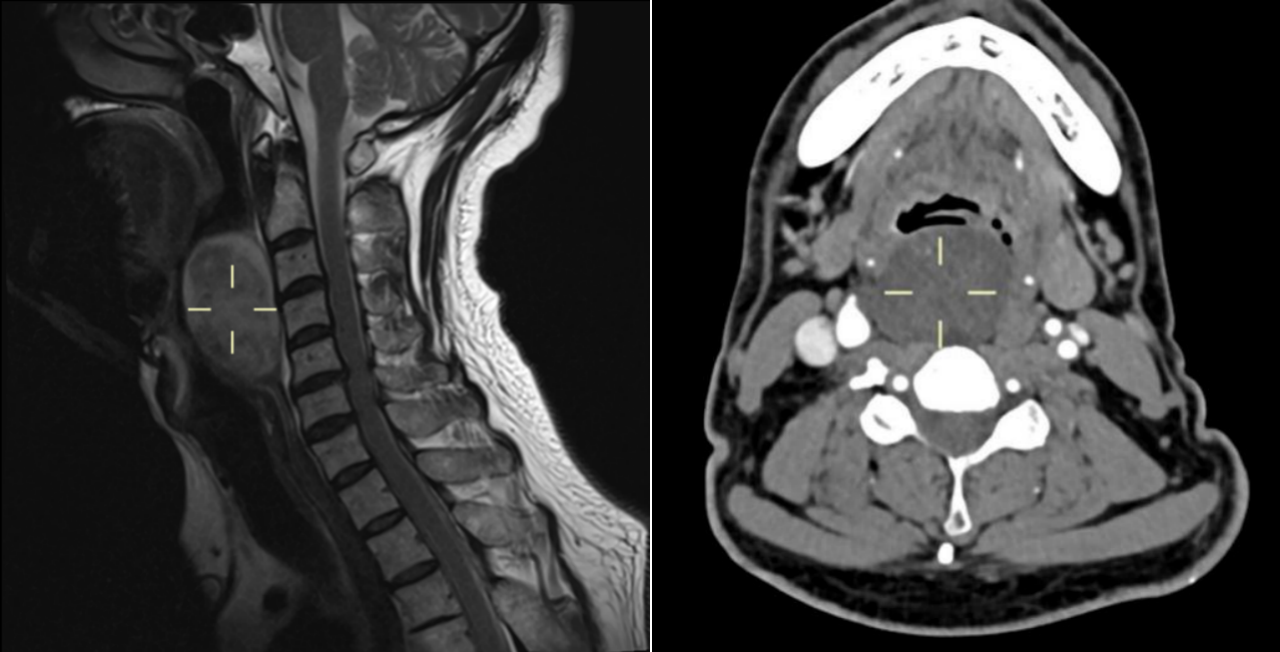

然而,进一步的鼻咽喉镜与增强CT检查显示,肿块体积庞大,几乎堵塞喉咽腔,其侧翼更是紧邻颈部大血管。这一特殊位置,使得常规全身麻醉下的声门暴露变得异常困难,传统方案往往需要先行气管切开,为手术建立气道。这无疑意味着万先生将不可避免地承受额外的创伤与疤痕。

面对这道关乎患者安全与生活质量的必答题,附属仁济医院多学科团队迅速集结。麻醉科主任医师朱辉领衔的气道管理小组,根据万先生的影像资料,制定了周密的“清醒纤支镜插管技术”方案。手术中,在高流量氧气的护航下,对患者进行局部麻醉与适度镇静,随后纤支镜精准引导气管导管穿过因肿块挤压而异常狭窄曲折的咽喉,直达安全区域,成功建立了气道。这一关键步骤不仅为后续手术扫清了障碍,也避免了气管切开带来的创伤。